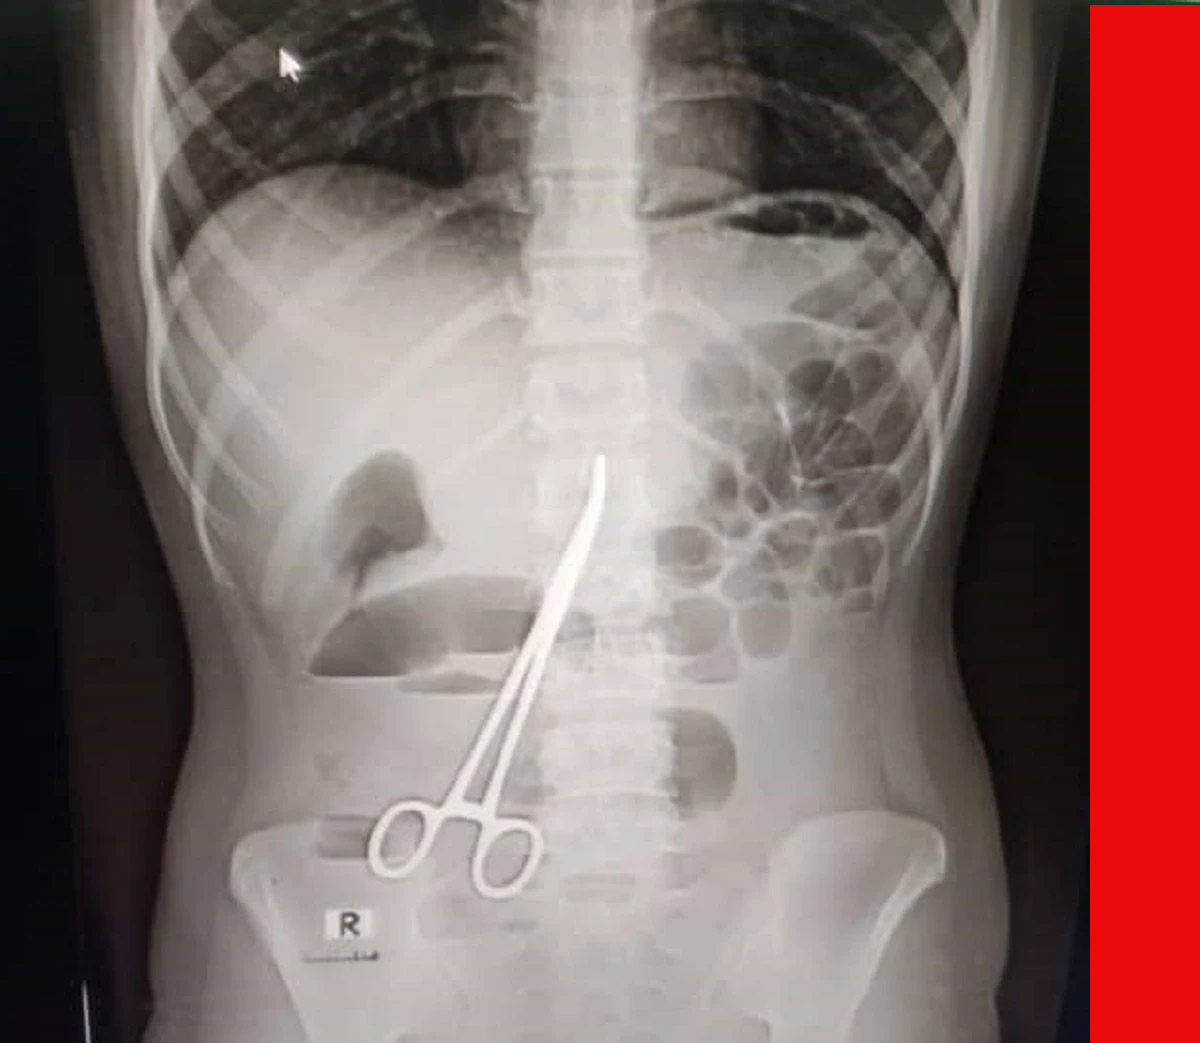

বিভিন্ন গ্রাম্য চিকিৎসা করানো হয়, কিন্তু তার পেট ব্যথা কমেনি। গত দু’দিন আগে পেটে অসহনীয় ব্যথা উঠলে তাকে মুকসুদপুরের একটি বেসরকারি ক্লিনিকে চিকিৎসার জন্য আনা হয়। ওই ক্লিনিকে এক্সরের মাধ্যমে চিকিৎসকরা দেখতে পান, মনিরার পেটের মধ্যে একটি ঝকঝকে কাঁচি আছে।

এ বিষয়ে মুকসুদপুর স্বাস্থ্য কমপ্লেক্সের কয়েকজন চিকিৎসক জানান, আমাদের সন্দেহ হলে তাকে একটি এক্সরে করতে বলি। পরে এক্সরে রিপোর্ট আসার পর কাঁচি দেখতে পাওয়া যায়। কয়েকজন চিকিৎসক বলছেন, গত বছরের ৩ মার্চ একটি অপারেশনের সময় ভুলে তার পেটের ভেতরে এ কাঁচিটি রেখে দেয়া হয়েছিল।

চিকিৎসকরা বলেছেন, ওই কাঁচির হাতলে সামান্য মরচে পড়ে গেছে এবং ওই যুবতীর পেটের ভেতরের অঙ্গ-প্রত্যঙ্গের সাথে জড়িয়ে গেছে এটি। দ্রুত অপারেশন করে কাঁচিটি বের করা না হলে রোগীর অবস্থা আরও খারাপ হতে পারে বলে জানান তারা।